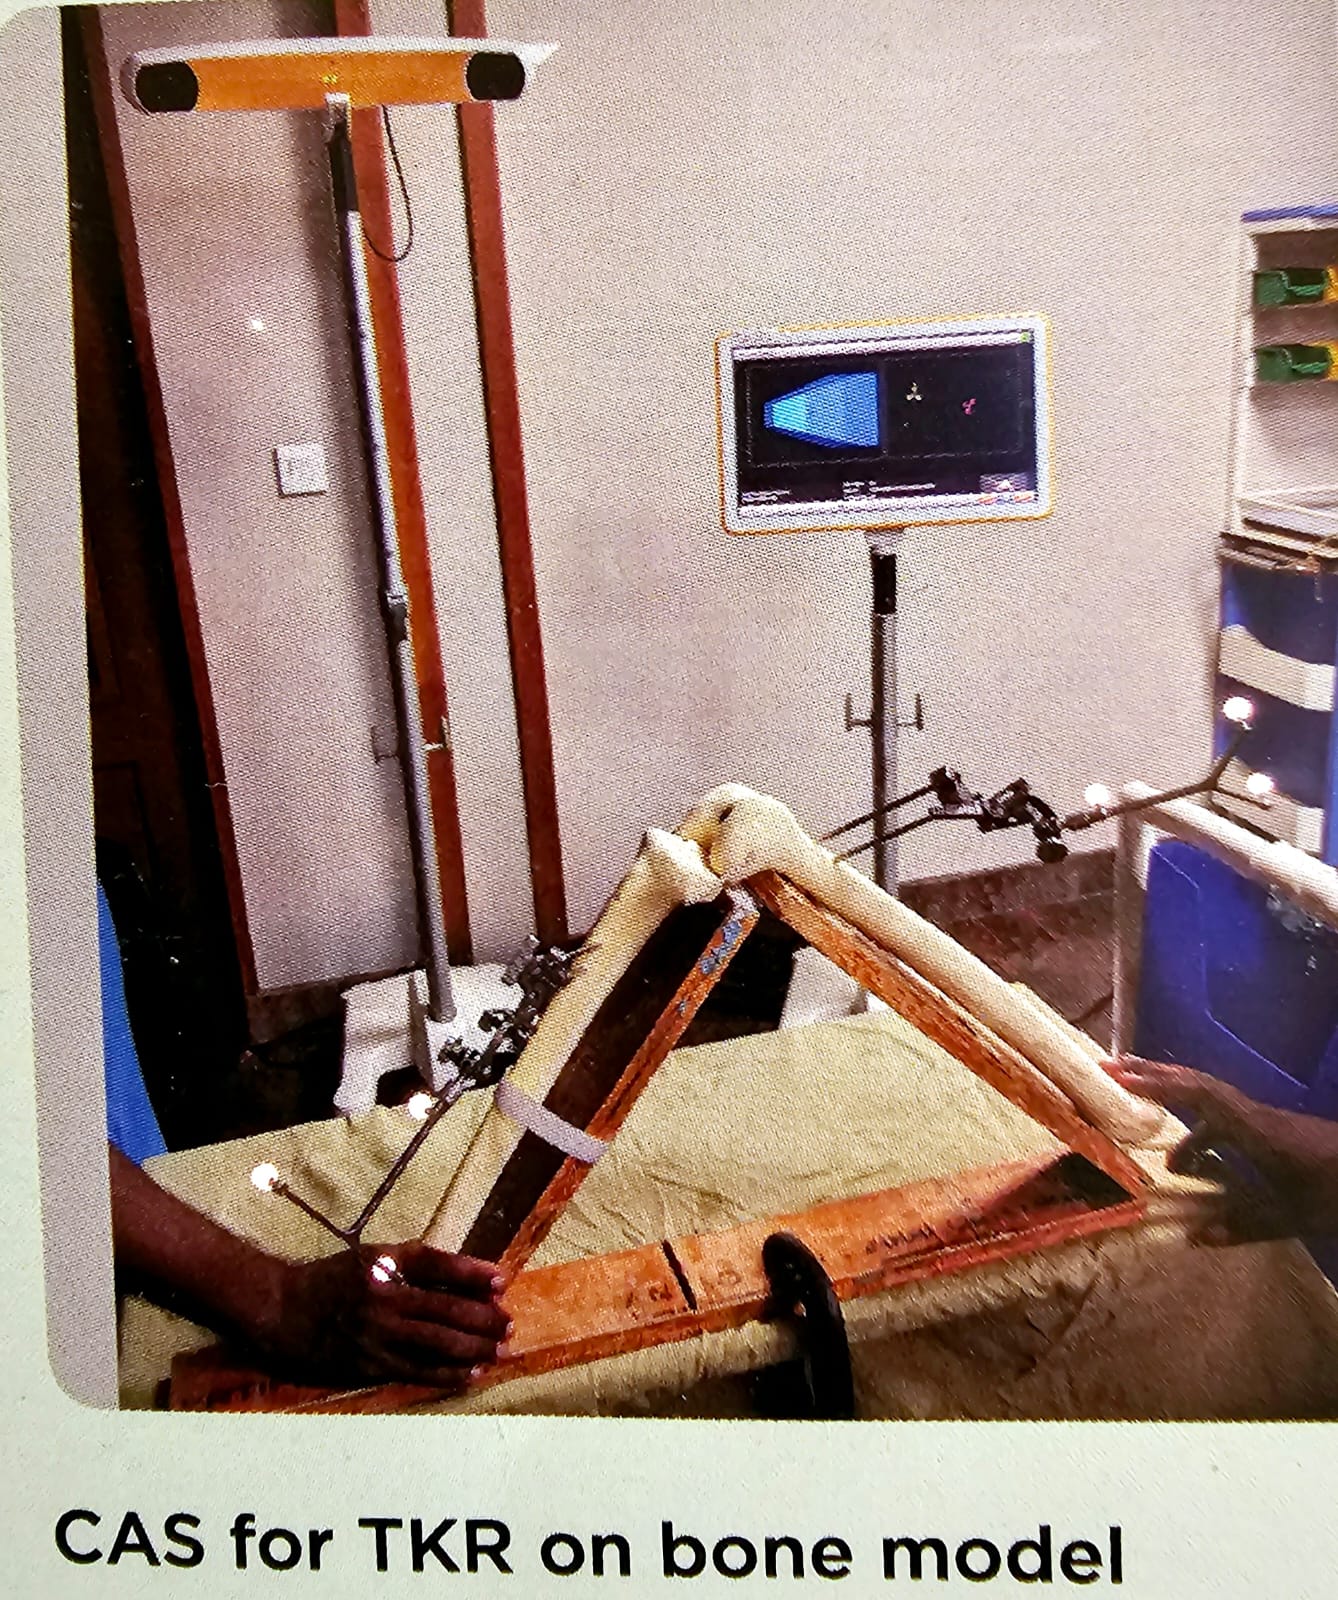

CAS for TKR on bone model

This picture demonstrates computer assisted surgery, for TKR on a bone model. You can see that the bone arrays are directed towards the T screen of the computer